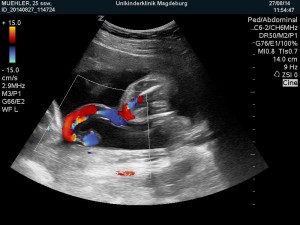

Heute gab es ein Fotoshooting der besonderen Art beim Opa auf Arbeit. Sein Kollege, der stellvertretende Chefarzt der Kinderklinik und gleichzeitig Guru des Ultraschalls, hatte sich bereit erklärt den werdenden Eltern noch ein paar aktuelle Fotos zu machen. Leider gab es kein 3D, aber dafür ein paar süße Fotos und vor allem Videos unseres Sohnemannes, der sich die ganze Zeit über ruhig verhielt und sich der Kamera, äh dem Schallkopf stellte.